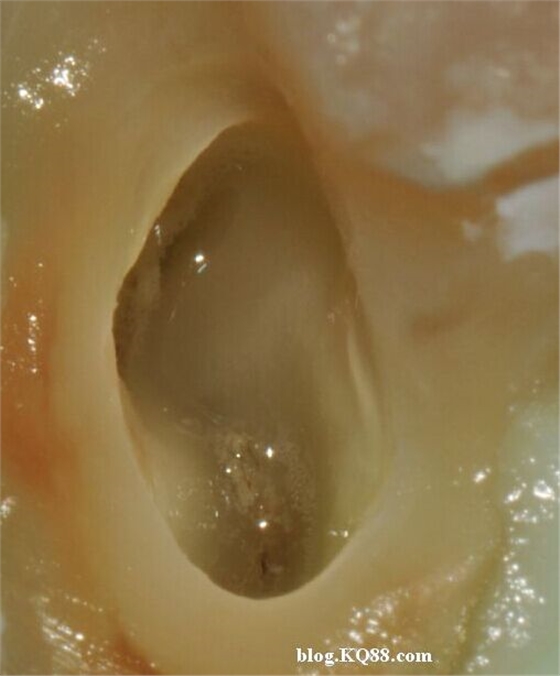

利用兩組照片說明:A因齲拔除的智齒去腐揭髓頂后

暴露牙髓

髓腔內(nèi)放入2%左右的次氯酸鈉,通過氣泡可以看到牙髓已經(jīng)開始溶解。